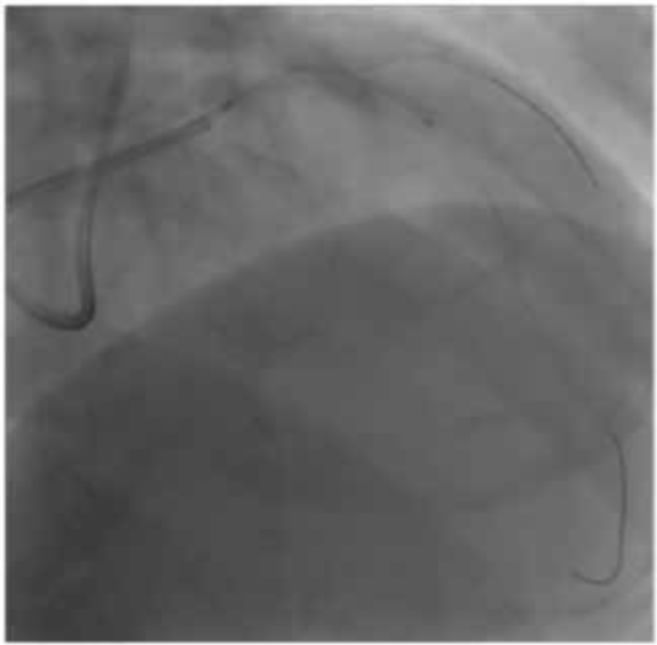

利用 3.5 mm SDB/2.0 mm LAXA进行KBT、支架贴壁良好。结束手术。

总结

本例中LCA的搭冠困难,但并不是通过更换导管,而是特殊操作设法使其同轴并得到良好的支撑性。如果没有ASAHI导引导管与冠脉口稳固结合这一特性,就需要更换其他导管了。另外3.5mmSDB进行后扩张时球囊依然推进困难,可将其作成α圈状提高支撑性,使球囊顺利通过。ASAHI导引导管兼具柔软性,支撑性和抗热变形性,使我们避免了必须更换新球囊的情况。